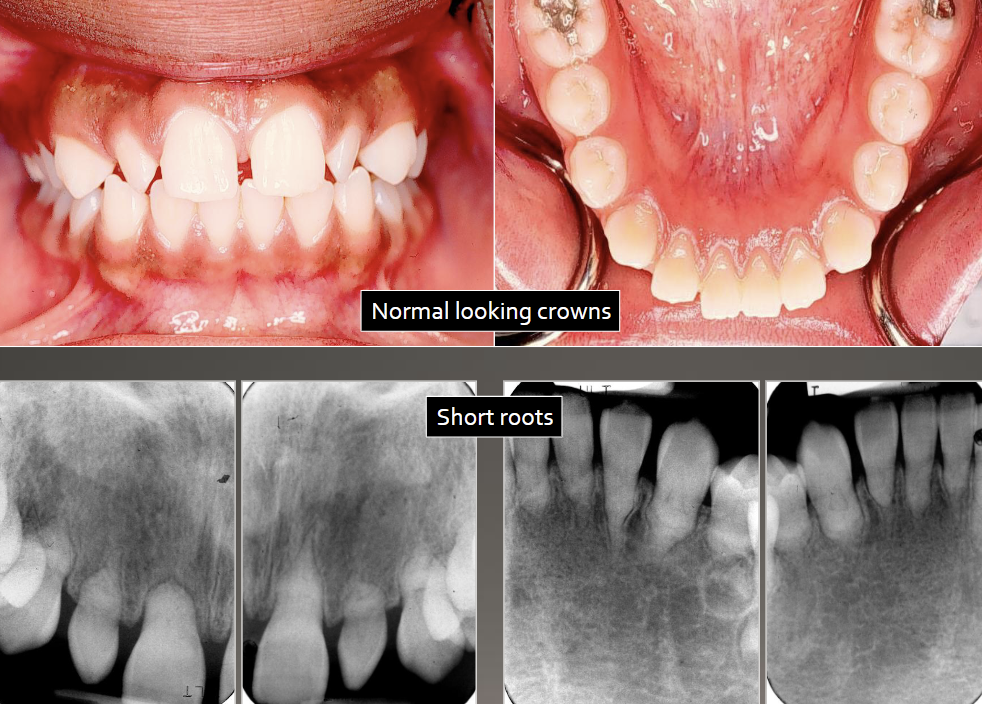

DGI radiographic presentation

bulbous crown, cervical constriction, pulp obliteration varies, expanded pulp = shell teeth

4 types, normal clinical crown, short roots, periapical radiolucencies, chevron pulp chambers

DD-I

have a blue-amber-brown translucence, bulbous crown, cervical constriction, thin roots, normal length, early obliteration of pulp

DD-II primary teeth

have a normal color clinically, pulp chamber is enlarged = thistle tube or flame shaped, pulp stone, normal root

DD-II permanent teeth